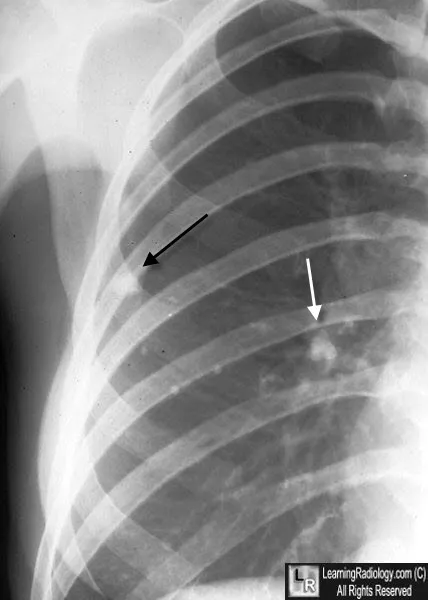

- Ghon Focus: Initial subpleural caseating granuloma.

- Ghon Complex: Ghon focus + hilar lymphadenitis.

⭐ The Ranke complex is a calcified, healed Ghon complex, representing the most common outcome in immunocompetent hosts.

- CXR: Hilar/paratracheal lymphadenopathy is the hallmark.

- Miliary: Disseminated; "millet seed" on CXR.